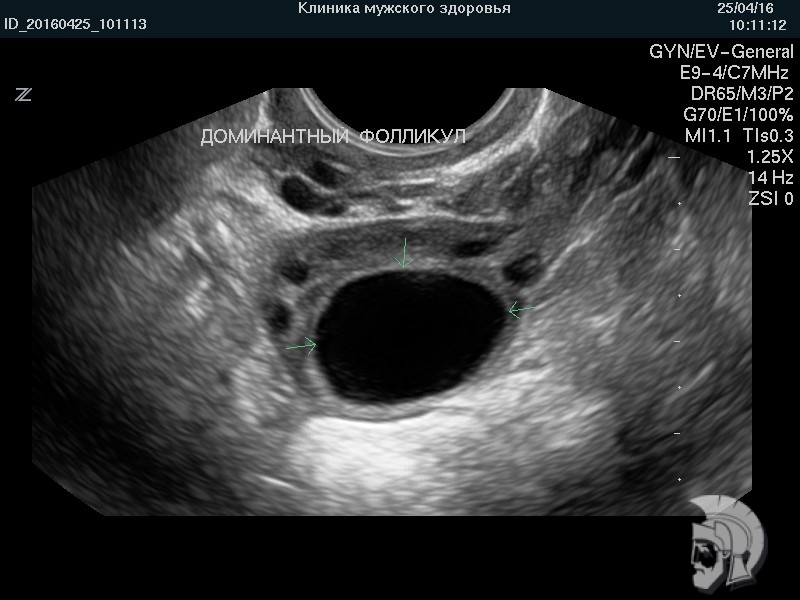

| Фото фолликулометрии. Созревший (преовуляторный) фолликул в яичнике указан стрелками |